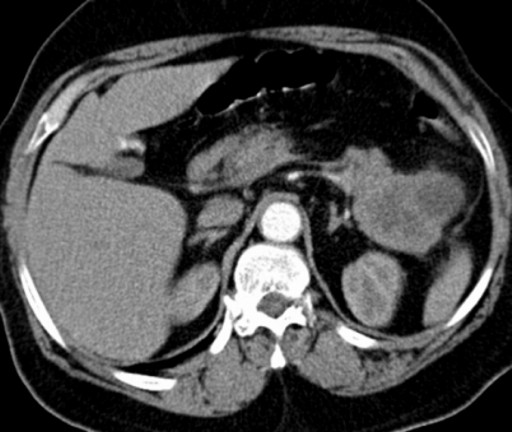

On August 2000, a 58-year-old female presented with large bowel obstruction, secondary to a malignant growth in the descending colon. She underwent an emergency left hemicolectomy and made an uneventful recovery. Histology showed moderately differentiated adenocarcinoma involving the serosal fat. The resected margins were free of tumor; however, 3 of the 18 regional lymph nodes were positive. The pathological staging was T3 N1 M0 and she received adjuvant chemotherapy which involved 6 cycles of FOLFOX chemotherapy (5-flurouracil and folinic acid and oxaliplatin). She was monitored regularly with ultrasound of the abdomen, carcinoembryonic antigen levels biannually and colonoscopy yearly for 2 years. The ultrasound of the abdomen was normal, carcinoembryonic antigen levels ranged between 2.2 and 4.7 µg/L (reference range: 0-2.5 µg/L) and colonoscopy showed small polyps which were benign. In March 2009 there was a sharp rise in carcinoembryonic antigen levels to 25 µg/L associated with a vague backache. A CT scan of the abdomen revealed a mixed density mass lesion with soft tissue and cystic components, measuring 6.8x4.8 cm in the area of the tail of the pancreas with possible left perinephric fat infiltration (Figure 1). No other metastasis was detected. A CT-guided biopsy suggested the possibility of adenocarcinoma. In April 2009, she underwent an exploratory laparotomy which revealed that the tumor in the distal pancreas was infiltrating the perinephric fat, the posterior wall of the stomach and the great omentum. She underwent a distal pancreatectomy and excision of the involved segment of the stomach, omentum and perinephric fat (Figures 2 and 3). Histology was reported as moderately differentiated adenocarcinoma with infiltration into the perinephric fat and the resected segment of the stomach. The adenocarcinoma was metastatic tumor from the colon confirmed by its histological appearance and strong positivity to cytokeratin 20 (Figures 4 and 5). The margins of the resected pancreas and stomach were clear of the tumor. She made an uneventful recovery. She received palliative chemotherapy in the form of 5 cycles of 5-flurouracil, oxaliplatin and bevacizumab. In October 2009, she presented with a mass in the left hypochondrium which on CT of the abdomen was found to be recurrent disease. She was provided care for the terminally ill and she ultimately died in January 2010, nine months after the resection of the metastatic tumor.

Figure 1. Mixed density lesion seen in the tail of the pancreas: metastatic tumor from cancer of the descending colon. |